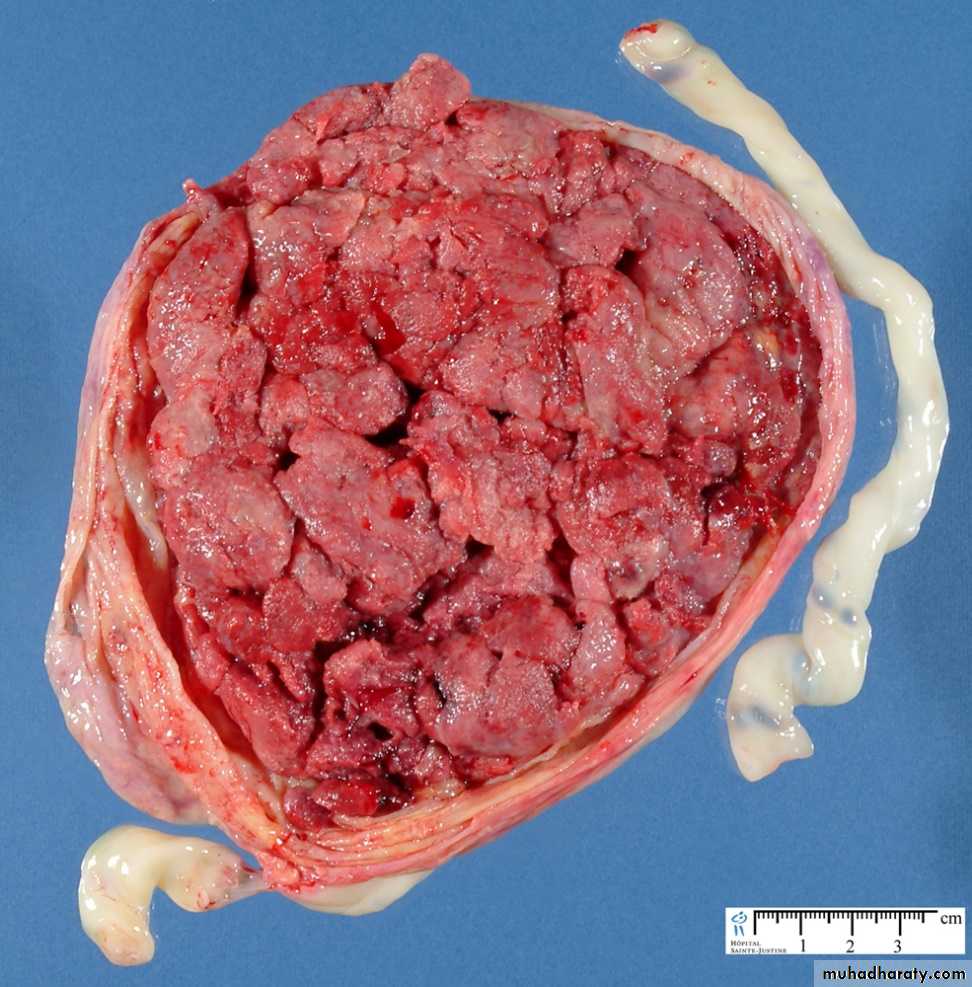

Maternal surface of the placenta

A == normal placenta

B == placenta perviaC == placenta accurate (abnormal placentation)

D == placenta abruption (premature sepration of the placenta)